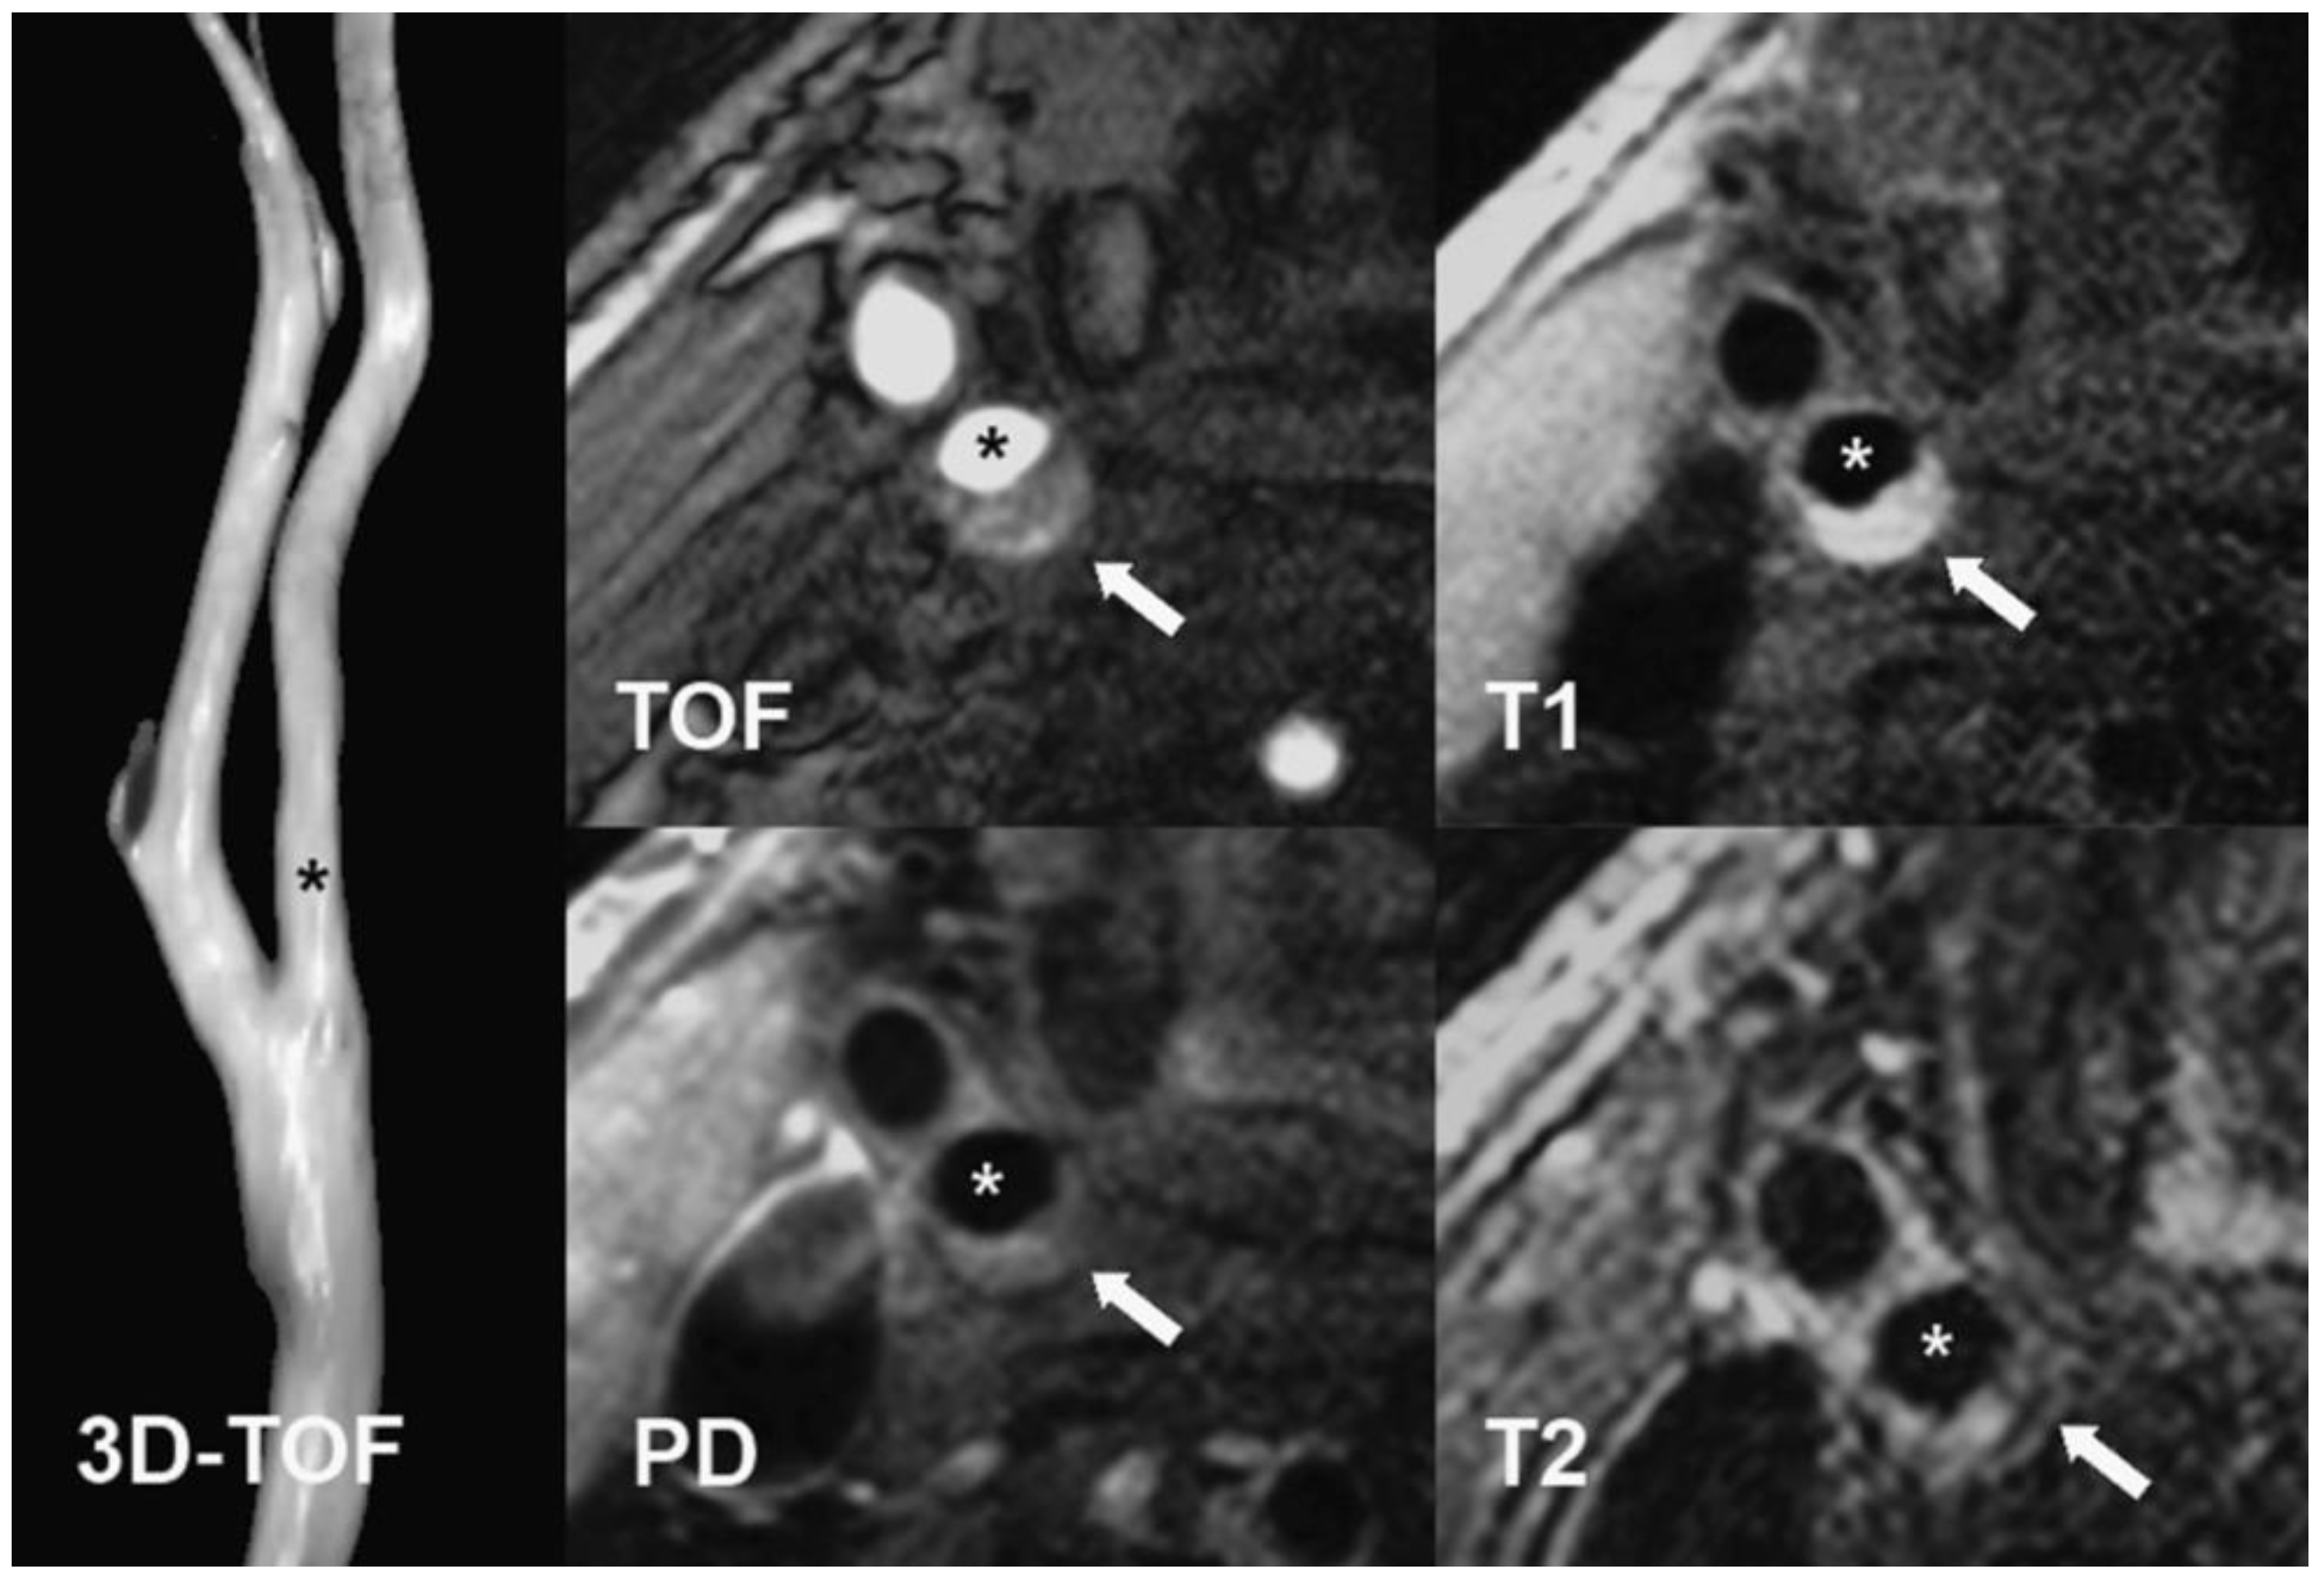

4.3. MRI Protocol

Sixteen participants were investigated with Carotid MRI. The examination was performed on a 1.5 T scanner (General Electric OPTIMA 450 w) with a HeadNeck 8-channel coil. The protocol included TOF (time-of-flight), T2-weighted (2D FIESTA), and T1-weighted (3D TRICKS) sequences, with dynamic contrast enhancement at the following parameters: 1. 2D FIESTA sequence in axial, coronal and sagittal planes at slice thickness = 4 mm with spacing = 1 mm, TR/TE = 4.4/min full, flip angle = 70°, matrix 224 × 320, NEX = 1.0. 2. 3D TOF in axial plane at slice thickness = 2.4 mm with overlap = 1.2 mm, TR/TE = min full/min full, flip angle = 35°, matrix 384 × 256, NEX = 1.0. Dynamic contrast enhanced (DCE) images were acquired with intravenous injection (0.2 mmol/kg) gadolinium contrast (Prohance) using the TRICKS sequence with parameters 3. 3D TRICKS in coronal plane at slice thickness = 2.2 mm, TR/TE = 3.7/min full, flip angle = 20°, matrix 352 × 224, NEX = 0.75. Total scan time was up to 40 min. Based on MRI results, participants were divided into subgroups according to AHA [65] modified criteria, and 10 were in the IV–V class. This group consists of plaques with a lipid-rich or necrotic core, surrounded by fibrous tissue with possible calcification. Moreover, 6 subjects were classified into the VI category, which includes plaques with possible surface defects, IPH, or thrombus. Carotid MRI was performed only once, before the start of the pharmacotherapy (Figure 4).

Figure 4.

Carotid MRI protocol.